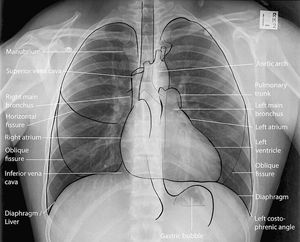

Chest X-Ray shows the mediastinal visible structures

The main focus is on the heart and diaphragm. You can also note the trachea after it is divided into right and left main bronchus.